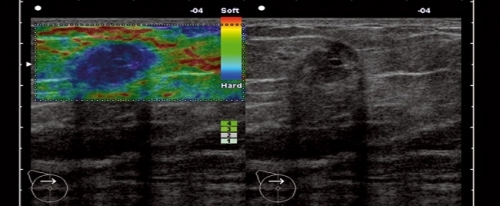

Inventată de specialiștii japonezi, sonoelastografia este o tehnică nouă, care măsoară elasticitatea tumorilor mamare. Tehnica masoară proprietățile de elasticitate cu ajutorul ultrasunetelor și se bazează pe faptul că țesutul malign (canceros) este mai dur decât țesutul benign. Această metodă poate detecta și localiza tumorile atunci când au o elasticitate diferită de țesutul mamar adiacent, fiind complementară mamografiei și ecografiei mamare.

Sonoelastografia aduce elemente suplimentare de caracterizare a leziunilor mamare, în funcție de elasticitatea lor, foarte importante mai ales în diferențierea tumorilor mai puțin tipice ca aspect față de celelalte metode. Sonoelastografia nu înlocuiește mamografia sau ecografia mamară, ci le completează, uneori fiind esențială pentru diagnosticul diferențial între un nodul mamar benign de unul malign. În final, diagnosticul de certitudine este cel anatomo-patologic, care se obține în urma efectuării unei biopsii.